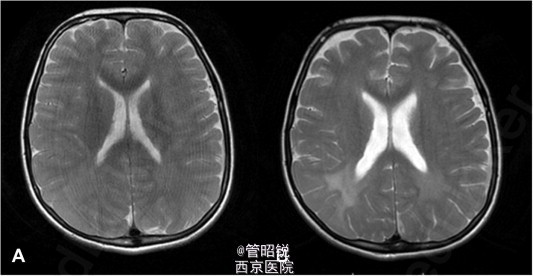

以帕金森特点发病的亚急性硬化性全脑炎 患者,男,12岁。主诉站立和行走困难2月。神经学检查示全面性肌强直、运动迟缓、姿势反射受损和面具脸征。初始诊断为儿童性帕金森病。但服用左旋多巴,安坦、和氯硝安定后无明显改善。EEG显示如下图。随后考虑SSPE,即亚急性硬化性全脑炎,脑脊液麻疹抗体的检出证实了这一诊断。